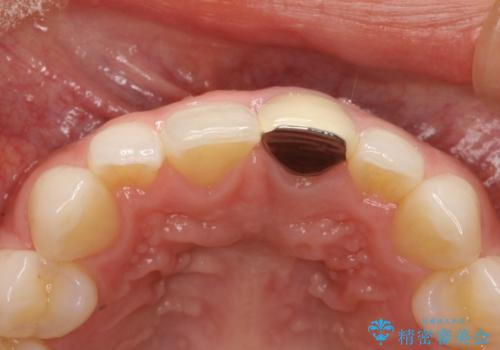

- 以前装着された前歯のかぶせ物の色を変えたいとのことで来院されました。

土台からの再治療を行い、オールセラミッククラウンを装着する治療計画としました。